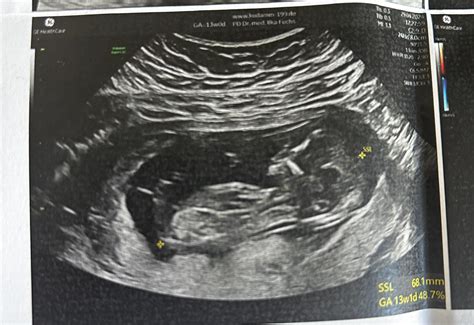

• Fetal Measurements: The healthcare provider will measure the baby's crown-rump length (CRL), which is the distance from the top of the head to the bottom of the buttocks. This measurement helps determine the baby's gestational age and growth rate.

• Anatomy Check: The ultrasound will assess the baby's anatomy, including the brain, spine, heart, kidneys, and limbs. This check helps identify any potential abnormalities.

• Placenta and Amniotic Fluid: The provider will also examine the placenta and the amount of amniotic fluid surrounding the baby. Adequate amniotic fluid is essential for the baby's development and movement.